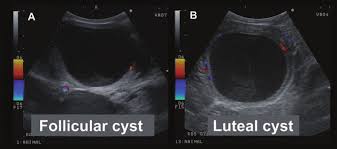

Types of Ovarian cysts

Follicular (thin walled) vs Luteal (thick walled, may produce progesterone)